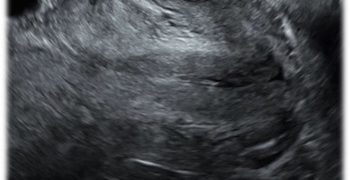

How To Do Gennaio 2021: Ecografia nelle Lacerazioni Ostetriche dello Sfintere Anale

Cari soci, il 2021 si apre con un interessante video "How to do", sul ruolo dell'ecografia nella diagnosi delle lacerazioni ostetriche dello sfintere anale. Grazie a Federica Bellussi! Il video...